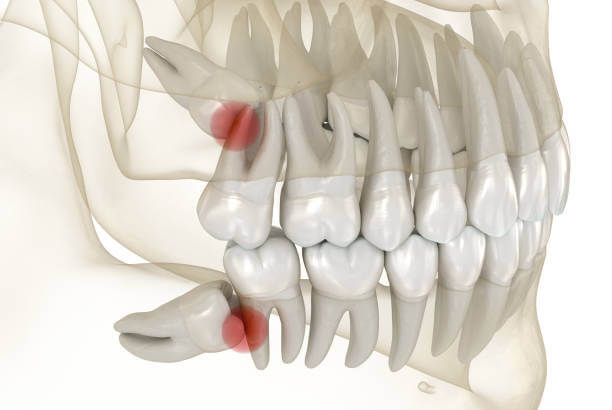

인류의 턱이 작아지면서 입안 깊숙이 사랑니가 자랄 공간이 부족해졌고 이 때문에 사랑니는 눕거나 발치하는 등 썩거나 염증이 생기기 쉬운 모양으로 나오는 경우가 많습니다.

사랑니는 다른 치아에 비해 크기와 모양이 매우 다양합니다. 사랑니는 똑바로 나오지 않고 기울어져 있거나 누워있는 경우 잇몸에 묻혀 있는 부분이 많습니다.

이 때문에 음식물 찌꺼기가 잇몸과 사랑니 사이에 끼기 쉽고 칫솔이 사랑니에 잘 닿지 않아 썩는 경우가 많고 제대로 청소하지 않으면 세균이 번식하고 염증이 생기기 쉬운 상태가 됩니다.

잇몸이 부어 오르거나 아플 때 감염이 느껴지고 위턱에 있는 사랑니가 부은 잇몸을 씹으면 더 불편 해집니다. 충치는 사랑니와 사랑니 앞 치아의 뒷면에도 형성될 수 있습니다. 이러한 충치는 종종 과소 검사되며 치통이 있을 때 가장 자주 발견됩니다. 심하면 양쪽 치아를 모두 뽑아야 하는 경우도 있습니다.

사랑니 주변에 염증이 생기면 잇몸이 붓고 볼이 붓고 침이나 음식을 삼키기 어려워지며 두통이 생깁니다. 목이나 턱뼈 안쪽으로 퍼지는 경우가 많아 입을 벌리기 어렵고 때로는 입원이 필요할 정도로 심한 사람들이 많습니다.